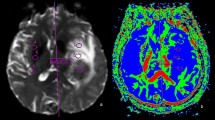

Initially, white matter hyperintensities in axial T2/FLAIR sequences of cerebral MRI were graded based on the Fazekas score [11]. In the manuscript, the term “T2-/FLAIR white matter hyperintensities” is replaced by the shorter synonymous term “white matter lesions” (WML). Degree of WML was defined as follows: no WML (grade 0), punctate WML (grade 1), beginning confluence of WML (grade 2) and large confluent areas (grade 3). Representative examples of WML grades are shown in Fig. 1.

Secondly, the NoM was determined on axial 3D T1-weighted sequences of cerebral MRI, and the maximum axial diameter of each individual metastasis was measured. Metastases situated in deep white matter were termed white matter metastasis (WMM) as these might have a different vascular background than metastases at the border of grey and white matter [12]. The per-patient mean diameter of all metastases (mDM) was determined.

In conclusion, there is increasing evidence for a negative correlation between small vessel disease and the number of brain metastases. WML may serve as a predictor of number and distribution of BM independent of tumor type. In future studies of this relationship quantitative MRI-measurements of brain perfusion e.g. like in [37] should be performed. Whether the knowledge about the negative impact of WML on BM may influence the treatment of BM remains to be answered in the future.